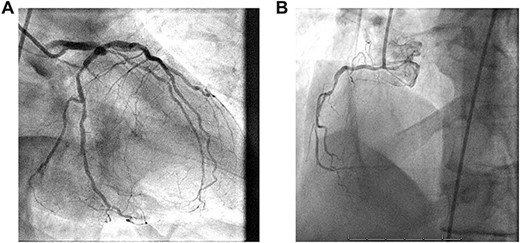

The patient is a 58-year old male who was being evaluated for inguinal hernia repair. His past medical history included CAD with prior stenting of the left circumflex artery, diabetes with a HbA1c of 5.7 and an 80-pack year smoking history. He reported a 37 kg unintentional weight loss over 6 months with postprandial abdominal pain and nausea. In addition, he had exertional angina relieved by rest and sublingual nitrates. He had an abdominal CT scan for evaluation of the hernia, and this demonstrated severe atherosclerotic abdominal aortic disease with occlusion of the origin of the celiac and superior mesenteric arteries and patency of the inferior mesenteric artery. This was confirmed by mesenteric angiography which demonstrated occlusion of the celiac and SMA with a large mesenteric collateral originating from the inferior mesenteric artery (Fig. 2). This artery had a 90% orifice stenosis. With his cardiac history and symptoms, he underwent coronary angiography, which demonstrated significant left main and 3-vessel CAD (Fig. 1A and B). Left ventricular function was preserved with no valvular heart disease by transthoracic echocardiography.

(A) 1. Left main coronary artery: large caliber vessel with distal 60% stenosis. 2. Left anterior descending coronary artery (LAD): large caliber vessel with proximal 80% stenosis gives rise to diagonals and septals. 3. Left circumflex coronary artery: large caliber, nondominant gives rise to OM 1 with proximal 70% stenosis before continuing with mid LCx 75% stenosis and distal 40% lesion. (B) Right coronary artery (RCA): medium caliber vessel that is dominant with proximal 85%, mid 85% and distal occlusion prior to PDA fills with left to right collaterals.